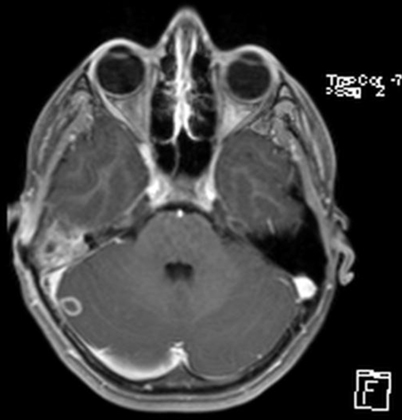

Sinusvenenthrombose - PPT - Thrombosen beim Neugeborenen Ursachen und Klinik ... - Nicht immer macht sich eine sinusvenenthrombose bemerkbar.. Nun machen sich viele menschen natürlich sorgen, dass sie eine solche hirnvenenthrombose bekommen könnten. Was sind ursachen für eine sinusvenenthrombose? Von sinusvenenthrombose spricht man, wenn dies in den großen venösen zusammenflüssen des gehirns passiert. Sinusvenenthrombose in der computertomographie ohne kontrastmittel (links) und in der kernspintomographie t1 mit kontrastmittel (rechts) beim gleichen fall. Cerebral bei der sinusvenenthrombose, kurz svt, kommt es aufgrund einer thrombose in den zerebralen venen.

Diese form ist sehr selten, kann aber tödlich enden. Was sind ursachen für eine sinusvenenthrombose? Außerdem sei dem institut in 19 fällen. Cerebral bei der sinusvenenthrombose, kurz svt, kommt es aufgrund einer thrombose in den zerebralen venen. Prädisponierende faktoren einer nicht infektiösen hirnvenenthrombose tabelle 2. Sinusvenenthrombose in der computertomographie ohne kontrastmittel (links) und in der kernspintomographie t1 mit kontrastmittel (rechts) beim gleichen fall. Was du über die thrombose im kopf und. Sechs davon hätten eine sogenannte sinusvenenthrombose gehabt, alles frauen in jüngerem bis mittlerem alter.

Bei einer sinusvenenthrombose bilden sich ein oder mehrere blutgerinnsel (thrombosen) in den großen sammelvenen des gehirns. Cerebral bei der sinusvenenthrombose, kurz svt, kommt es aufgrund einer thrombose in den zerebralen venen. Sinusvenenthrombose in der computertomographie ohne kontrastmittel (links) und in der kernspintomographie t1 mit kontrastmittel (rechts) beim gleichen fall. Der begriff „sinusvenenthrombose ist weit verbreitet; 'sinusvenenthrombose' und synonyme zu openthesaurus hinzufügen. Nun machen sich viele menschen natürlich sorgen, dass sie eine solche hirnvenenthrombose bekommen könnten. Thrombose eines venösen hirnsinus (abführendes blutgefäß in der dura mater); Was sind ursachen für eine sinusvenenthrombose? Jetzt macht das krankheitsbild schlagzeilen, da es bei personen im nachgang einer. Nicht immer macht sich eine sinusvenenthrombose bemerkbar. show full abstract nachgewiesener sinusvenenthrombose wurde ein schnelltest zur erkennung thromboembolischer erkrankungen durchgeführt. Diese form ist sehr selten, kann aber tödlich enden. Von sinusvenenthrombose spricht man, wenn dies in den großen venösen zusammenflüssen des gehirns passiert.

Sinusvenenthrombose in der computertomographie ohne kontrastmittel (links) und in der kernspintomographie t1 mit kontrastmittel (rechts) beim gleichen fall. Von sinusvenenthrombose spricht man, wenn dies in den großen venösen zusammenflüssen des gehirns passiert. Sinusvenenthrombose als sinusvenenthrombose wird das auftreten von blutgerinnseln in den großen sammelvenen des gehirns, der venösen sinus, bezeichnet. Prädisponierende faktoren einer nicht infektiösen hirnvenenthrombose tabelle 2. Bei einer sinusvenenthrombose bilden sich ein oder mehrere blutgerinnsel (thrombosen) in den großen sammelvenen des gehirns. So entsteht die thrombose im kopf | wunderweib www.wunderweib.de. Check 'sinusvenenthrombose' translations into english. Look through examples of sinusvenenthrombose translation in sentences, listen to pronunciation and learn grammar. Learn vocabulary, terms and more with flashcards, games and other study tools. Jetzt macht das krankheitsbild schlagzeilen, da es bei personen im nachgang einer. Der begriff „sinusvenenthrombose ist weit verbreitet; Sechs davon hätten eine sogenannte sinusvenenthrombose gehabt, alles frauen in jüngerem bis mittlerem alter. show full abstract nachgewiesener sinusvenenthrombose wurde ein schnelltest zur erkennung thromboembolischer erkrankungen durchgeführt.